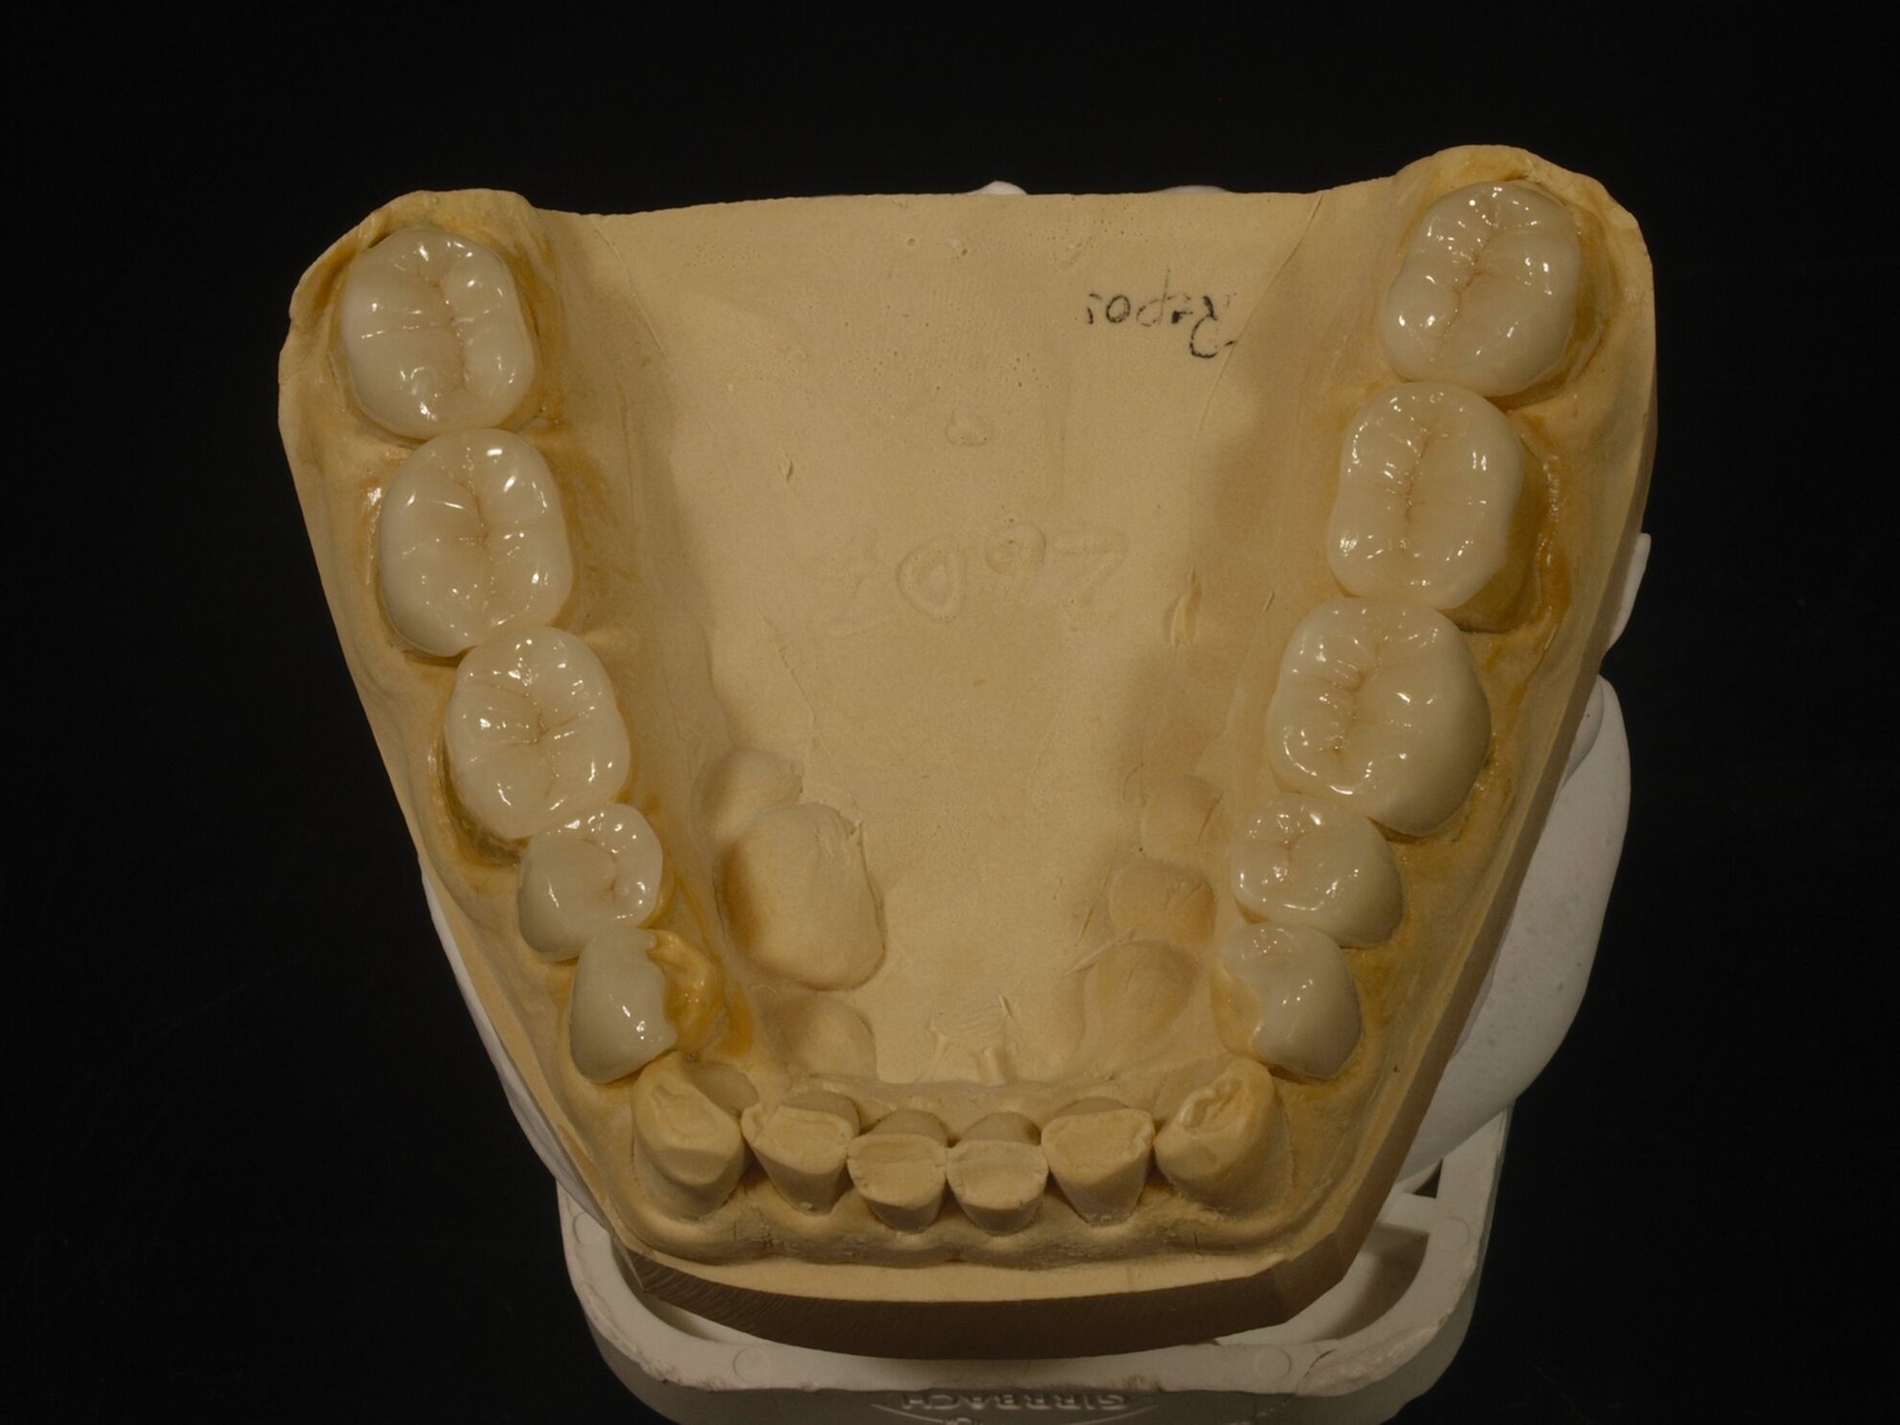

Diese Simulation der Okklusion bildet die Voraussetzung für das nachfolgende Wax-Up der geplanten Zahnform als zahntechnische Planungsgrundlage. Das so ergänzte Kiefermodell wird anschließend dubliert, als Grundlage der Herstellung neuer Kiefermodelle in neuer Kontur, auf denen wiederum speziell verstärkte Formteile für die spätere intraorale Ausformung der Komposite erstellt werden. Die Ausformung der Restaurationen aus Kompositen und ihre Aushärtung erfolgen insofern zwar intraoral „direkt“, das Gesamtvorgehen ist aber an die gleichen zahntechnischen Vorarbeiten gebunden wie eine Therapie mittels indirekter Restaurationen. Solchermaßen hergestellte Restaurationen überstehen nach Untersuchungen der engagierten Kollegen aus Zürich drei Jahre in gutem Zustand [Schmidlin et al., 2009]; nach fünf Jahren ist der Zustand allerdings beeinträchtigt [Attin et al., 2012].

Für die Behandlungsabfolge bestehen verschiedene Möglichkeiten, die unmittelbar mit der Kontrolle der Gelenkstellung verbunden sind. Generalisierter Zahnverschleiß erfordert häufig eine Behandlung aller Zähne zumindest eines Kiefers, weil der vertikale Platzbedarf zum Schutz der geschädigten Zähne eine Erhöhung der vertikalen Dimension erfordert. Dies bedingt insofern eine zeitgleiche Versorgung aller behandelten Zähne zumindest im Seitenzahnbereich, weil sonst eine ungleichmäßige Abstützung resultiert. Bewährt hat sich die Aufteilung derartig aufwendiger Behandlungen in mehrere Abschnitte. Dabei erfolgt im ersten Abschnitt die Abstützung im Seitenzahnbereich in neuer VD, in der Regel einhergehend mit einer semipermanenten Versorgung der Frontzähne zur Wiederherstellung der dynamischen Führung in neuer VD. Im begründeten Ausnahmefall kann dieser Schritt entfallen, etwa bei unmittelbar nachfolgend geplanter Behandlung der Frontzähne; in dem Fall erfolgt die Steuerung der dynamischen Okklusion in der Zwischenzeit mit einer entsprechend gestalteten Okklusionsschiene, die auch tagsüber getragen wird (Abbildung 11).

Nach der Eingliederung der Restaurationen hat sich eine umgehende Abformung bewährt, die ebenso umgehend in Modelle überführt wird, um zu prüfen, ob die Restaurationen gleichmäßig aufeinandertreffen. Beim Folgetermin zum Finetuning liegen diese dann vor und erlauben im Zweifelsfall eine umgehende okklusale Korrektur. Wichtig ist, den sensorischen Eingewöhnungsstress der Patienten abzufangen. Das gelingt am Tag der Eingliederung durch eine hydrostatische Sofortschiene (The Aqualizer, Bausch Dental, Köln; AquaSplint mini, TeleDenta, Chemnitz; FreeBite Gel, MediPlus, Unterleinleiter). Spätestens nach dem Finetuning erfolgt eine neue Abformung als Grundlage für die Herstellung einer neuen Okklusionsschiene. Die AWMF-Leitlinie zu vollkeramischen Kronen und Brücken verlangt, dass diese bei Bruxismus zum Schutz der Restaurationen dauerhaft getragen wird. Diese Okklusionsschiene kann im Ober- oder Unterkiefer getragen werden, die eingestellte Kieferposition entspricht der durch die Restauration eingestellten Position.